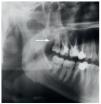

Se informó al paciente del diagnóstico y de la intervención prevista con anestesia general para la extracción de la aguja. Se practicó una incisión intraoral (fig. 3a) sobre la rama ascendente que no planteó problemas. Con ayuda de la fluoroscopia dinámica y una pinza mosquito como referencia se consiguió localizar rápidamente la punta de la aguja rota. A continuación, se consiguió sujetarla y extraerla sin contratiempos (fig. 3b). Se trataba de una aguja para inyección de calibre 30 y de 25 mm de largo (fig. 3c). El periodo postoperatorio transcurrió sin complicaciones.

Figura 3a. Incisión intraoral en la región de la rama ascendente.

Figura 3b. Fragmento de aguja visible durante la intervención. Retirada del fragmento con una pinza arterial fina.